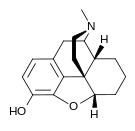

- Desomorphine (dihydrodesoxymorphine)

Desomorphine Desomorphine (Dihydrodesoxymorphine) |